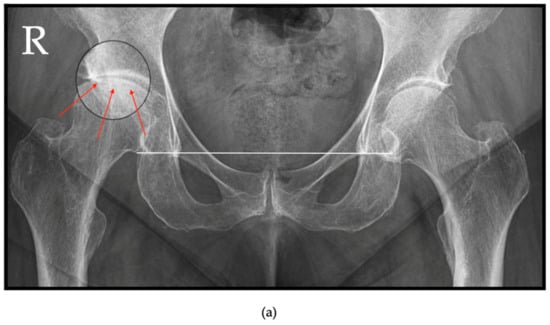

6.1. Radiographs

- Flemming, D.J.; Gustas-French, C.N. Rapidly progressive osteoarthritis: A review of the clinical and radiologic presentation. Curr. Rheumatol. Rep. 2017, 19, 42. [Google Scholar] [CrossRef]

- Nakamura, K.; Okamoto, Y.; Wakama, H.; Matsuyama, J.; Ishitani, T.; Otsuki, S.; Neo, M. T1 pelvic angle is associated with rapid progression of hip arthrosis. Eur. Spine J. 2023, 32, 1463–1470. [Google Scholar] [CrossRef]

- Rosenberg, Z.S.; Shankman, S.; Steiner, G.C.; Kastenbaum, D.K.; Norman, A.; Lazansky, M.G. Rapid destructive osteoarthritis: Clinical, radiographic, and pathologic features. Radiology 1992, 182, 213–216. [Google Scholar] [CrossRef]

- Chau, H.T.H.; Wong, P.Y.; Pan, N.Y.; Ma, K.F.J. Rapidly destructive hip osteoarthritis: A diagnosis not to miss. Br. J. Radiol. 2024, 97, 1526–1533. [Google Scholar] [CrossRef]